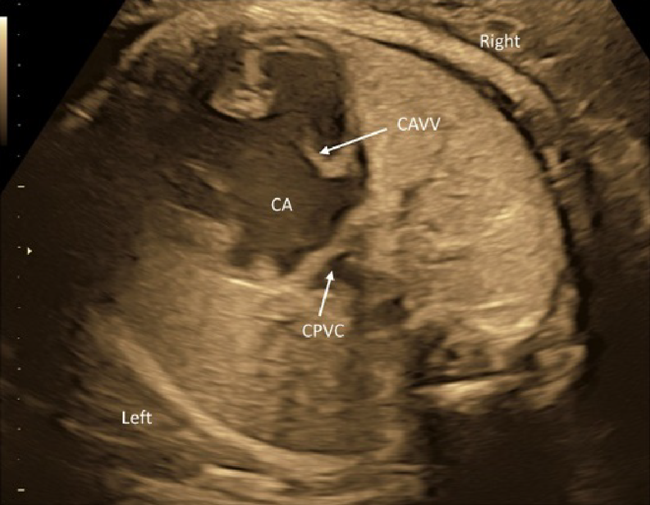

Supplement: Segmental Diagnosis of Congenital Heart Disease (Fig. 15)

Complicated congenital heart diseases are documented on the basis of segmental diagnosis. The cardiovascular structures are described in terms of arrangement of the atria, position of the ventricles, and orientation of the great arteries. Normal anatomy is denoted as S, D, N.

The morphologically right atrium is expected to have connection to the inferior vena cava. When the morphologically right atrium is found towards the right, it is in a standard position (described as solitus [S]). If the structure is found towards the left, it is in an inverse position [I] (Fig. 16). If the inferior vena cava and the descending aorta are on the same side of the body, or if the inferior vena cava is missing, it is classified as ambiguous (A). The laterality of the inferior vena caval return (if the inferior vena cava is missing, the position of the dilated azygos/hemiazygos vein is used) is classified as A(S) (right-sided) or A(I) (left-sided).